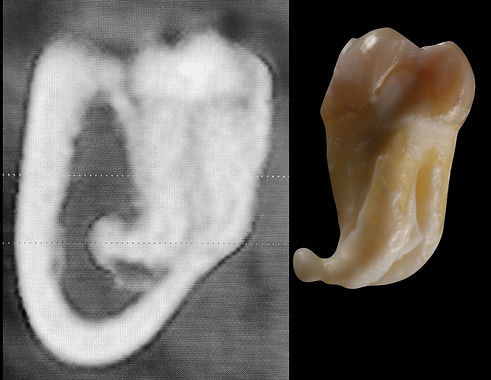

L'estrazione di un dente del giudizio, specialmente quello inferiore, è spesso complicata dalla sua posizione (vicino al nervo alveolare inferiore) o dal fatto che è "incluso" nell'osso. Con la tecnica tradizionale (fresa), il dentista deve rimuovere l'osso attorno al dente usando uno strumento rotante che taglia tutto ciò che incontra e genera molto calore.

Con la chirurgia piezoelettrica, invece: il chirurgo utilizza le micro-vibrazioni per rimuovere con precisione millimetrica solo il minimo strato di osso necessario per liberare il dente. Se lo strumento si avvicina o tocca il nervo alveolare (che trasporta la sensibilità del labbro e del mento) o i vasi sanguigni, non li lesiona, poiché vibra a una frequenza che agisce solo sui tessuti mineralizzati. Durante l'uso, lo strumento emette un getto d'acqua che, unito agli ultrasuoni, crea un effetto chiamato cavitazione. Questo non solo raffredda l'area (evitando di surriscaldare l'osso), ma aiuta a mantenere il campo operatorio pulito dal sangue, dando al chirurgo una visibilità perfetta.